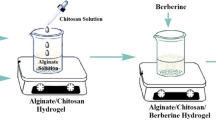

The synthesized nHAP had an average diameter of 212.33 ± 33.02 nm with the polydispersity index of 0.02. The injectable hydrogels were obtained after crosslinking their solutions with EDC at room temperature (Fig. 1). The concentration of 0.10 mM EDC was chosen according to the previous study by Priyadarshani et al. [26], in which they demonstrated that this concentration is optimal for maximal cytocompatibility. Since the positive effect of obtained hydrogels on the physiology of Schwann cells, as the major cells to support the repair and regeneration of injured peripheral nerves, is desirable [27, 28], the effect of hydrogels on the proliferation of Schwann cells was investigated in vitro. Incorporation of nHAP not only did not induce any toxic effect toward Schwann cells, it enhanced their proliferation (Fig. 2). The collagen + nHAP hydrogel displayed significantly higher absorbance values than the positive control (tissue culture plate) and collagen hydrogel after 48 h (P < 0.005) and 72 h (P < 0.05).